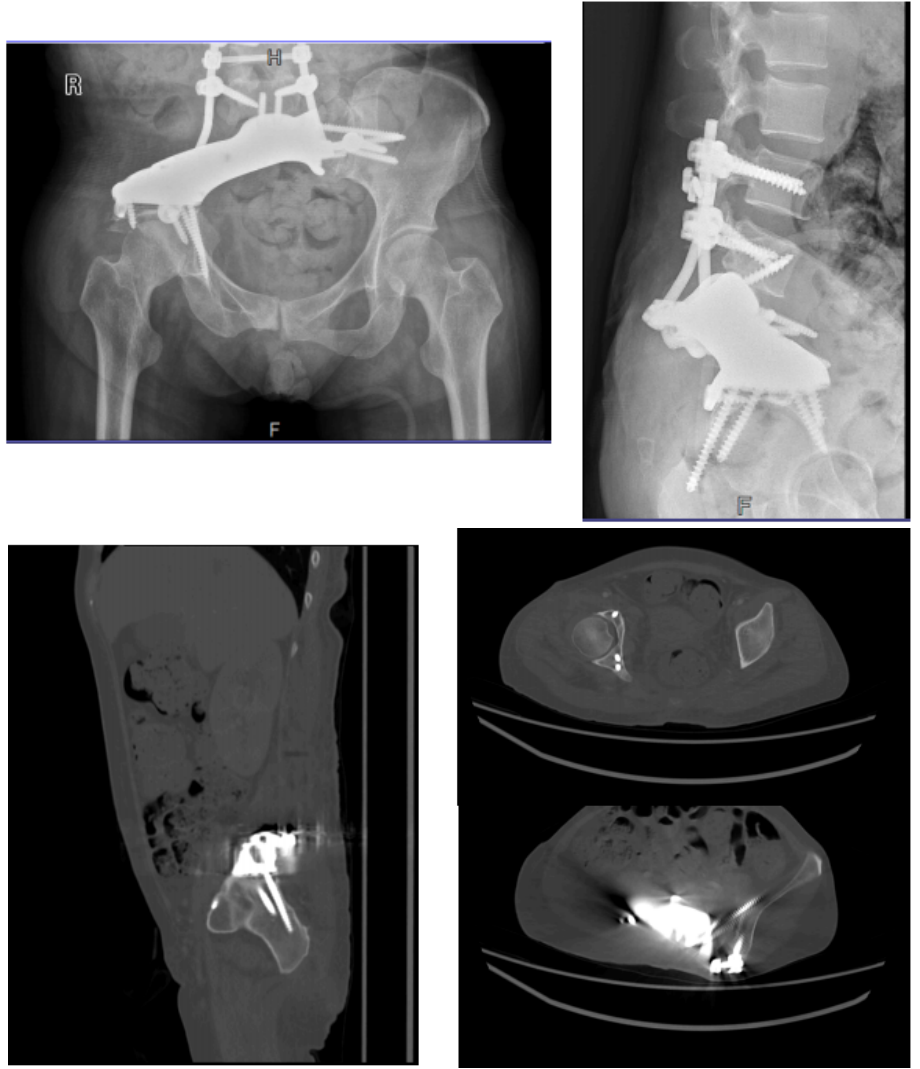

手术由骨肿瘤团队统筹,麻醉科、手术室、输血科等多科室协作完成。术中团队实施肿瘤根治性切除,并完成骨盆功能重建。术后影像学显示,定制型半骨盆位置良好,假体-骨界面有效接触。

图3术后复查影像学。定制型半骨盆位置良好,假体-骨界面有效接触。

为在根治性切除肿瘤的同时重建骨盆完整性,团队采用3D仿生打印技术,为患者定制了与骨盆缺损形态匹配的内植入假体。该假体基于患者术前高精度CT数据设计,表面具有多孔结构,可诱导自体骨细胞长入,实现假体与骨界面的生物融合,从而增强远期稳定性,为术后功能恢复创造条件。